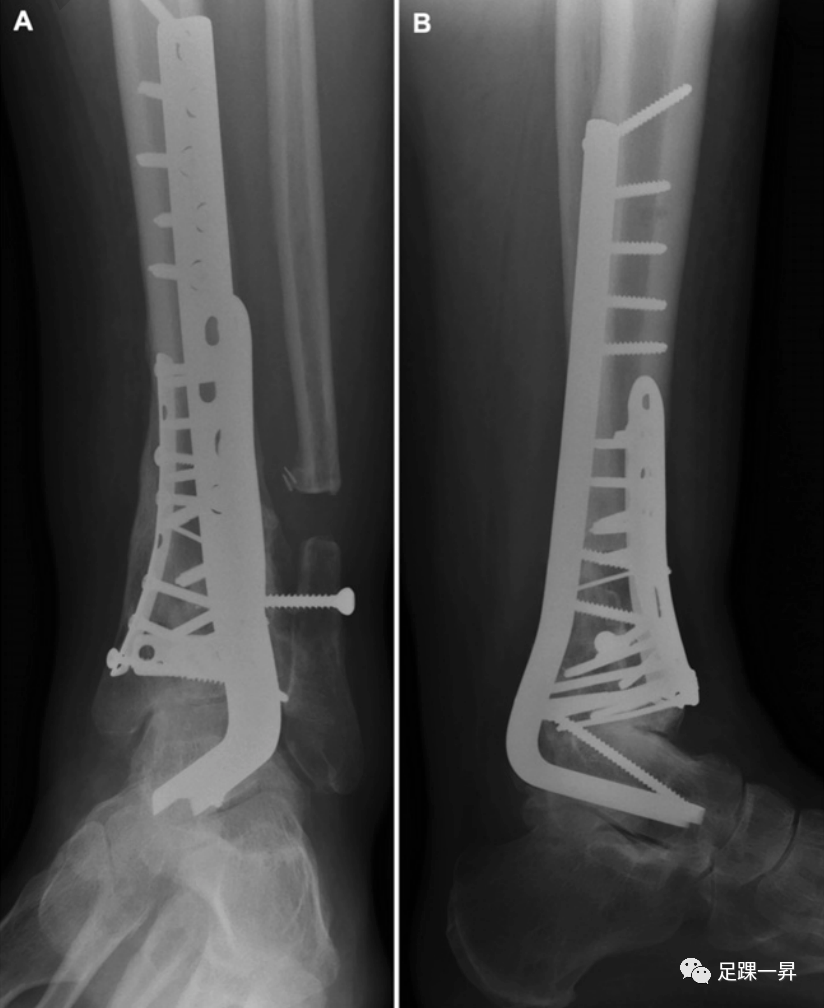

Pilon骨折手术的标准前路方法已得到充分描述。后侧入路也有很好的描述,可以在传统固定中发挥补充作用,直接复位和/或固定特定骨折碎片,并松解嵌顿的软组织结构。部分关节(OTA/AO型-43B)的手术入路相对简单,由移位的关节碎片区域决定。完全性关节(OTA/AO型-43C)损伤需要根据原发骨折线的位置以及关节面压缩区域采用个体化方法。已经提出了各种详细描述骨折复位和固定的手术技术。通常,具体的前路切口和肌腱间隔是基于前外侧(Chaput)和内侧骨折块之间骨折线的位置; 通过这些骨折块的间隙可以进入后方和进入压缩区域(图5)。直接内侧入路可用于支撑内侧柱避免内翻塌陷。

△图示Pilon骨折的术中照片,其中Chaput骨块和内侧骨块之间的骨折线被“翻书样打开”,以便于更靠后地接近压缩区域。一旦后侧复位工作完成,将Chaput骨块和内侧骨块复位并进行固定。

一项关于Pilon骨折手术入路的系统综述发现,与后外侧和前内侧入路相比,直接前路和内侧入路的并发症发生率较低,包括伤口并发症和骨不连。在另一项评估手术入路对Pilon骨折术后感染风险影响的研究中,未检测到相关性。已报告的并发症发生率差异可能是由于软组织的状况和血供所致。每种骨折和患者都必须单独考虑,以优化关节复位和软组织愈合。